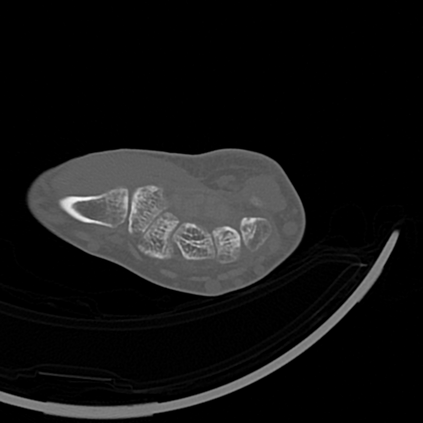

CT reconstruction provides radiologists with images for diagnosis and treatment, yet current deep learning methods are typically limited to specific anatomies and datasets, hindering generalization ability to unseen anatomies and lesions. To address this, we introduce the Multi-Organ medical image REconstruction (MORE) dataset, comprising CT scans across 9 diverse anatomies with 15 lesion types. This dataset serves two key purposes: (1) enabling robust training of deep learning models on extensive, heterogeneous data, and (2) facilitating rigorous evaluation of model generalization for CT reconstruction. We further establish a strong baseline solution that outperforms prior approaches under these challenging conditions. Our results demonstrate that: (1) a comprehensive dataset helps improve the generalization capability of models, and (2) optimization-based methods offer enhanced robustness for unseen anatomies. The MORE dataset is freely accessible under CC-BY-NC 4.0 at our project page https://more-med.github.io/